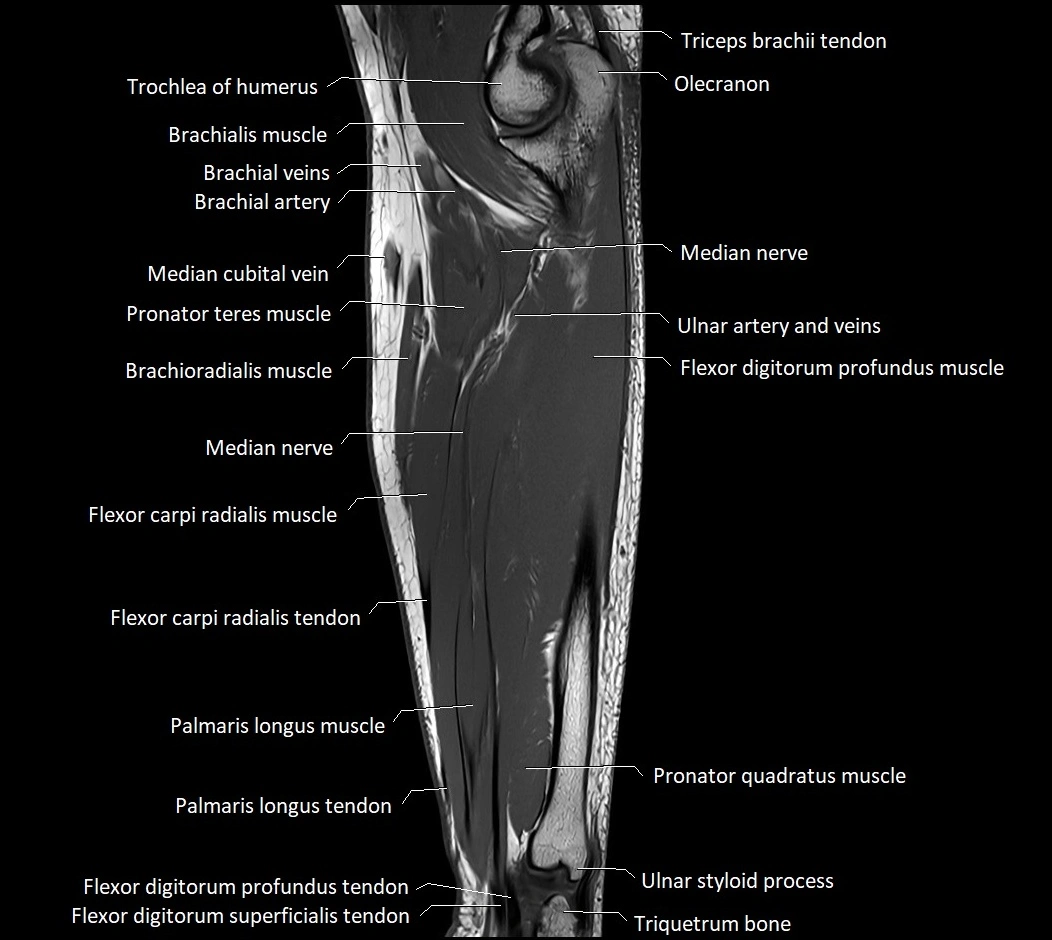

MRI images

image